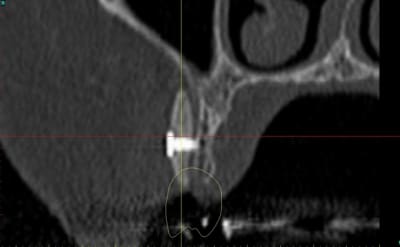

dentiste57 écrivait:

--------------------

> et là ?

> greffe selon ta méthode ?

Cross section dhvkc8 - Eugenol

3d dt3qom - Eugenol

Overview uqcp6u - Eugenol

S2y2o1v7q53ws4r5wy6ou8czrpom - Eugenol

pxav

01/05/2011 à 12h55

> dentiste57 écrivait:

> --------------------

> > et là ?

> > greffe selon ta méthode ?

expansion, c'est plus cool!